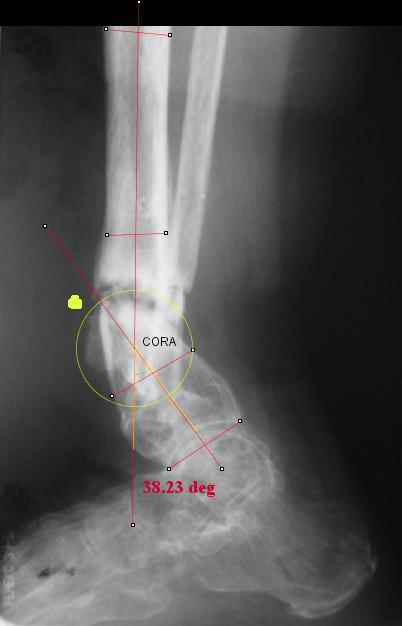

Maybe my "embedded software" is obsolete but it hints me to place hinges at the yellow point - this must result with alignment and some lengthening without translation. What do you think?

I think that if you locate the hinge at that site and then you rotate the foot about this point with out distraction you will be perfectly lined up. If you distract in the axis of the proximal tibia then rotate, it should still work (the hinge should still be located in the mid tibial axis). But, if you distract out of that axis then you will get translation. Does that make sense?

I looked at your image. I presume your yellow marker is the hinge axis? I think this should be at the CORA.